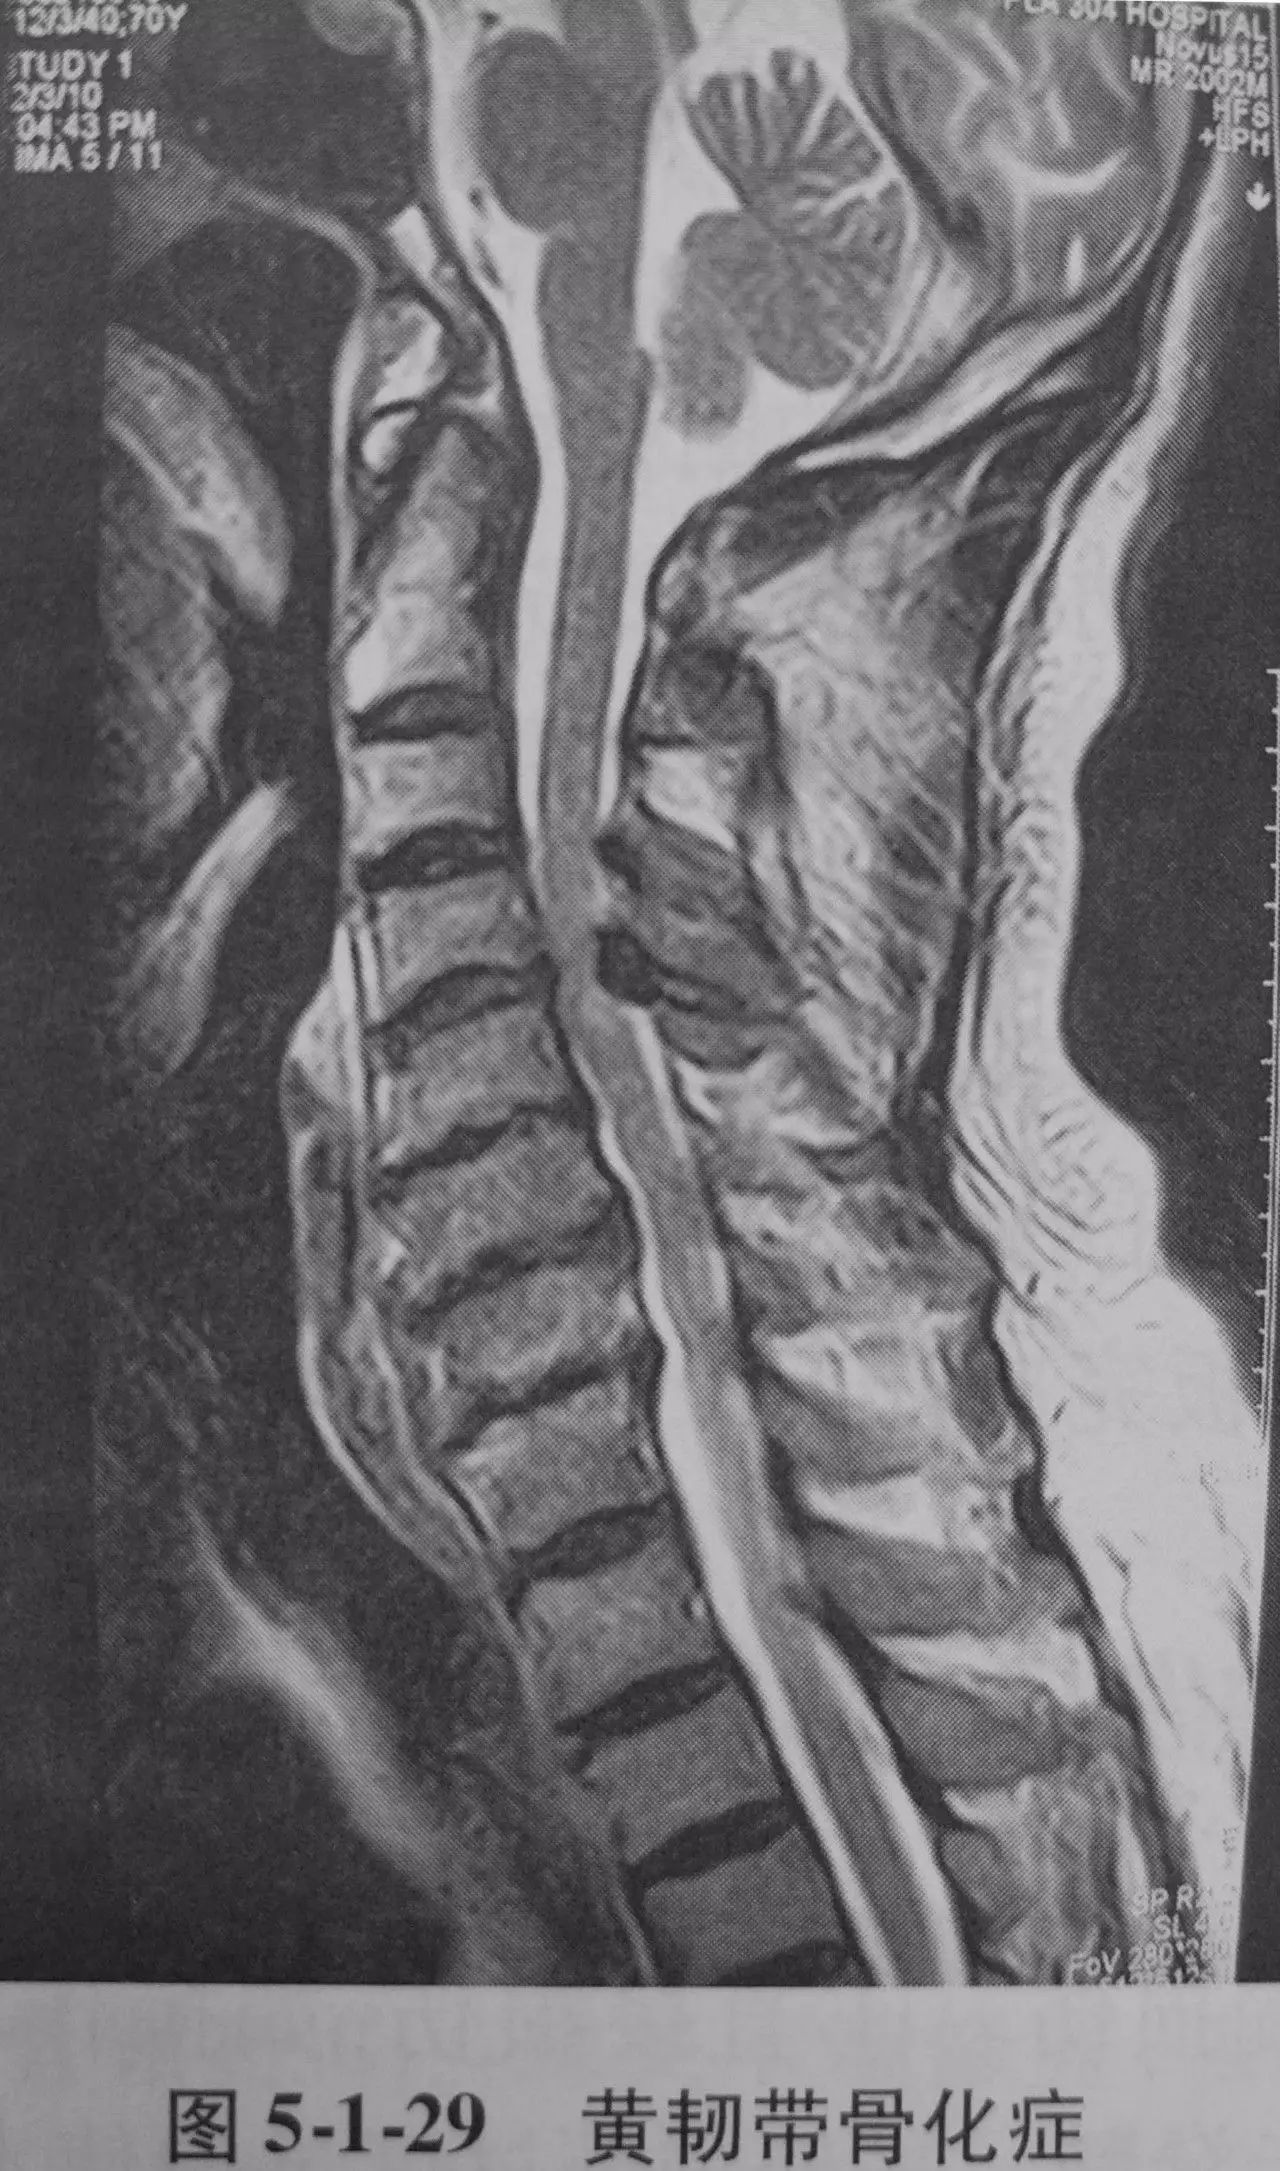

黄韧带骨化症、颈椎椎板棘突肿瘤、颈椎肿瘤需全椎板切除等可以行后路椎板切除术。可以使脊髓神经根减压,同时做后路椎弓根侧块螺钉内固定等,亦可重建颈椎稳定,减轻疼痛,保护脊髓、神经根功能等。除根据症状体征结合辅助检查,确定病变的节段部位外,有无椎板畸形对术中辨认结构确认节段很有意义。病灶定位一定要结合颈椎正侧位片。

1、适应证黄韧带骨化症、颈椎椎板棘突肿瘤、颈椎恶性肿瘤需全颈椎切除术、椎管内肿瘤等。

4、对于黄韧带骨化骨块压迫脊髓,应在骨块四周压迫较轻的部位咬除,使骨块游离,然后提起骨块,用神经剥离子分离骨块与硬膜之间的粘连,取出骨块。即使再轻柔的操作,也难免对脊髓有刺激,所以在进行此步骤前,先应用脱水药物和激素,以增加脊髓的耐受性。